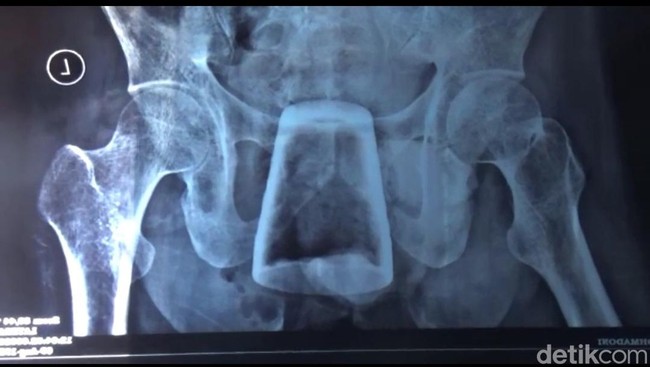

Gelas di dalam perut pria di Jember (Yakub Mulyono)